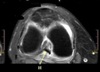

INFRASPINATUS MUSCLE

How well did you know this?

1

Not at all

2

3

4

5

Perfectly

10

Q

What is letter D?

A

GLENOID